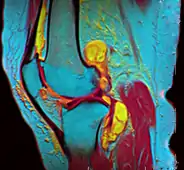

A pseudocolor MRI of a knee created using three different grayscale scans – tissue types are easier to discern through pseudo color.